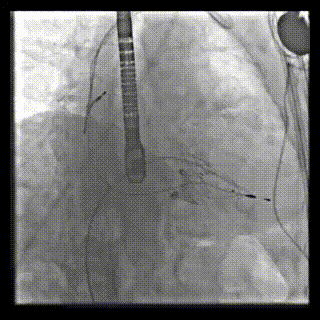

患者二术中DSA

图片